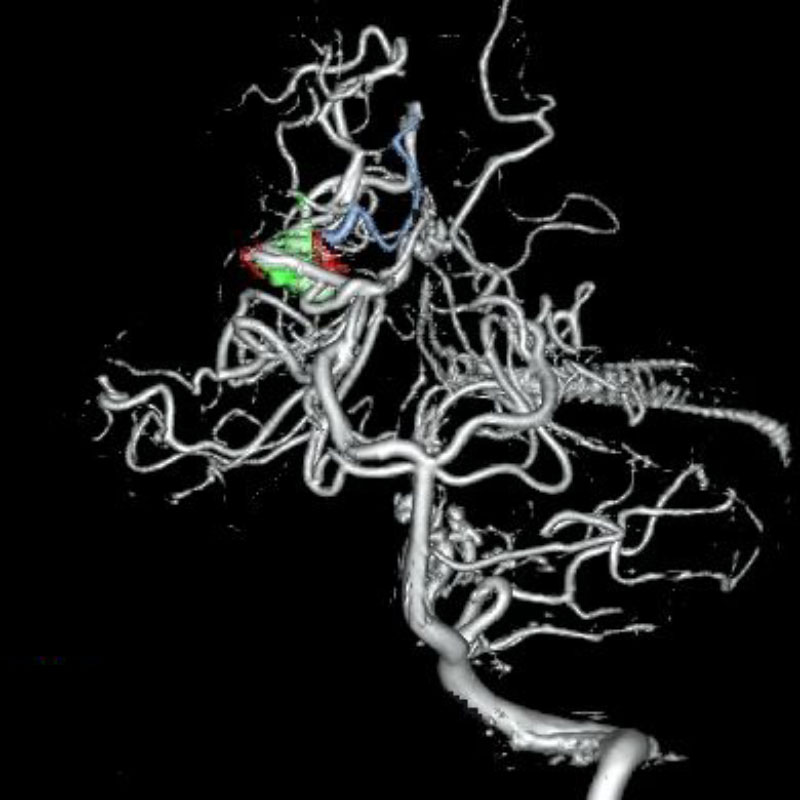

'19年5月

30代

富永/久貝

右中小脳脚 出血再発

SM 3(S1,E1,V1)

米国の病院

No.359 モニタリング

No.359 手術前

No.359 手術中

No.359 手術後

出血既往があり。2回の手術前血管内手術の後に、

Lateral transpeduncular approachにより再々出血予防を目的に

摘出手術を行う。完全摘出であることを確認した。

手術による合併症や後遺症なしで退院した。経過良好。